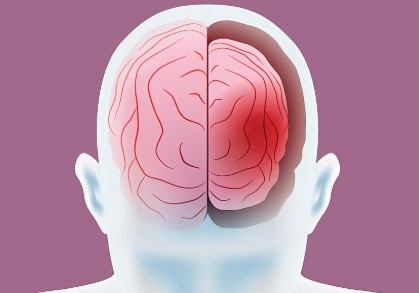

MEDICAL SHOCKER: Anti-psychotic medications SHRINK the BRAIN by 10 percent, according to peer-reviewed research and whistleblowing psychiatrist

(NaturalNews) Brain Volume Reduction:Â Psychotropic drugs can reduce brain volume by 8 to 11 percent, as revealed in studies on Macaque monkeys published in…